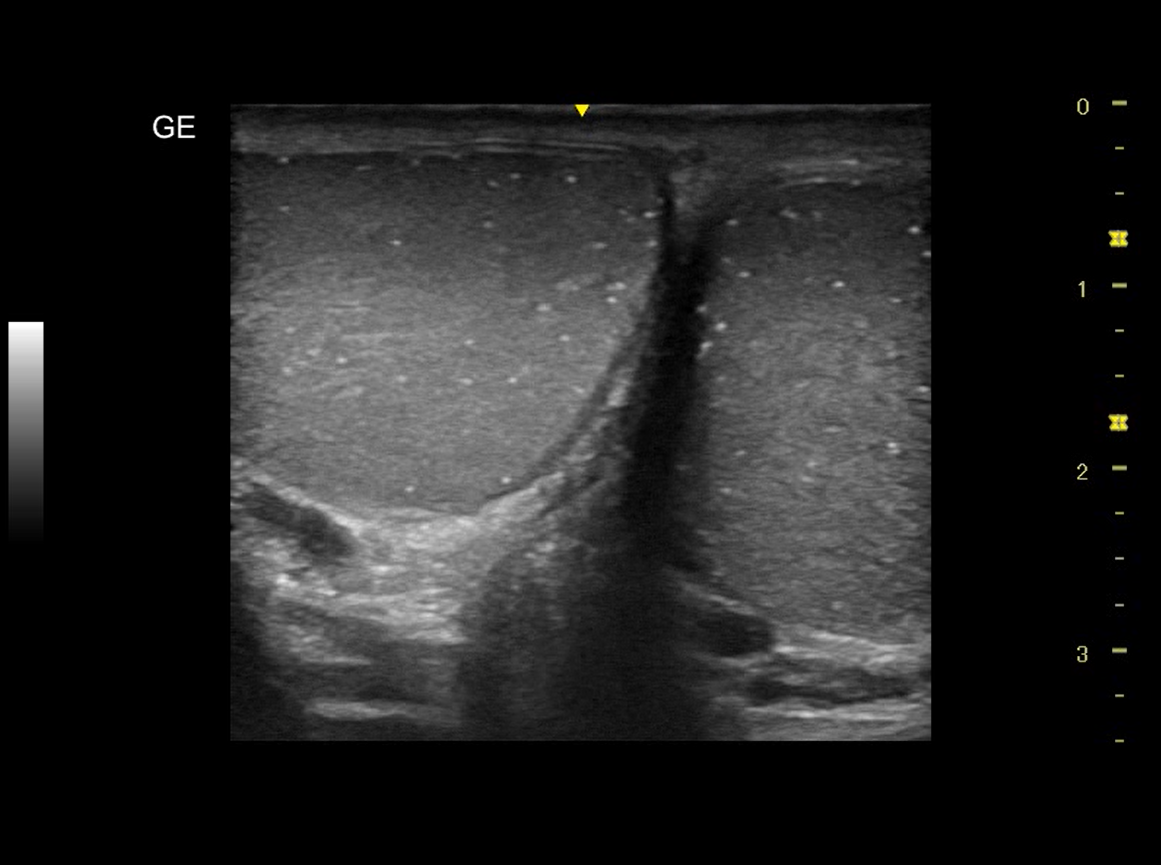

Realizamos ecografía clínica testicular: observamos ambos testículos con microlitiasis bilaterales puntiforme sin sombras acústicasen, en forma de cielo estrellado, vascularización normal, cabeza epidídimo izquierdo con leves signos inflamatorios, mínimo hidrocele.

Microlitisis testicular bilateral en contexto de Orquiepidimitis aguda. Diagnóstico diferencial con tumor testicular, torsión testicular, absceso testicular, hidátide.